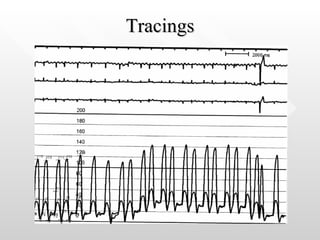

Tracings

What is the differential diagnosis for these tracings? How do we make the diagnosis?

What is thedifferential diagnosis for these tracings? How do we make the diagnosis?